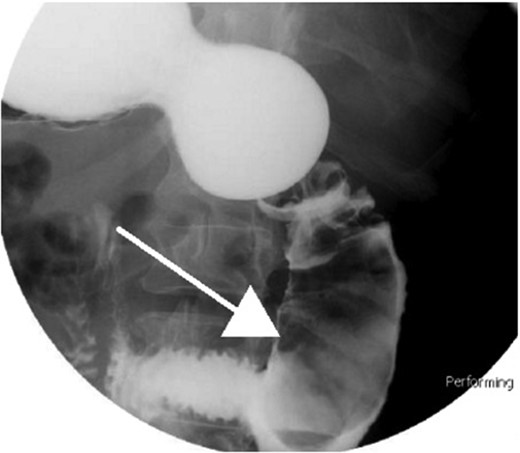

Small bowel series showing duodenal filling defect (posterior view).

Small bowel series showing duodenal filling defect (anterior view).

With regard to diagnostic workup, the literature has described cases with similar results to ours. Small bowel contrast studies frequently show smooth-walled polypoid filling defects within the duodenal bulb, and CT imaging is useful for delineation of adjacent structures including the common duct and pancreas [1]. Moreover, similar to the pathological results found in our patient, upper endoscopy biopsies are often equivocal as they are submucosal-based lesions [1]. The most useful diagnostic study, however, is endoscopic ultrasound, which may help distinguish the consistency and bowel layer of origin [2, 6], which unfortunately was not available at our institution.